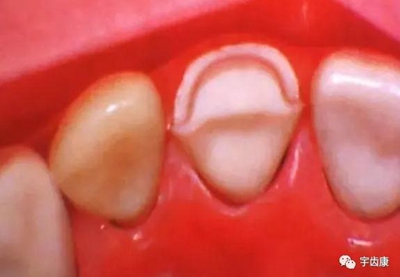

防止過度預(yù)備(造成牙髓激惹)

保留活髓(保留牙體的整體性和韌性)

過度預(yù)備抗力形喪失

4. 預(yù)留修復(fù)體的空間